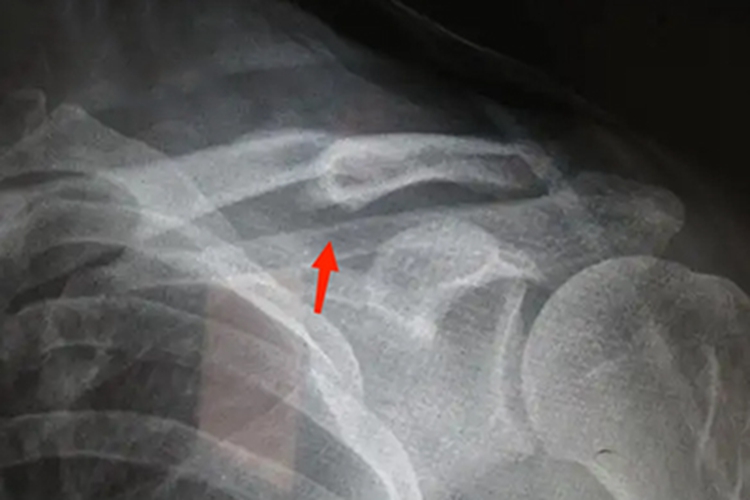

锁骨骨折畸形愈合是锁骨骨折的并发症,指骨折愈合的位置未达到功能复位的要求,存在成角、旋转或重叠畸形,骨折部位的旋转移位、分离移位没有完全矫正。

影响骨折愈合的因素有很多,骨折复位不佳、固定不牢固或过早拆除固定物、骨折断端受肌肉牵拉、胳膊的重量和不恰当负重的影响,都可导致畸形。

锁骨骨折愈合后稍有畸形、不会影响上肢功能者无需特殊治疗,若出现血管或神经受压迫的症状,或严重影响外观,需再次行切开复位内固定术。